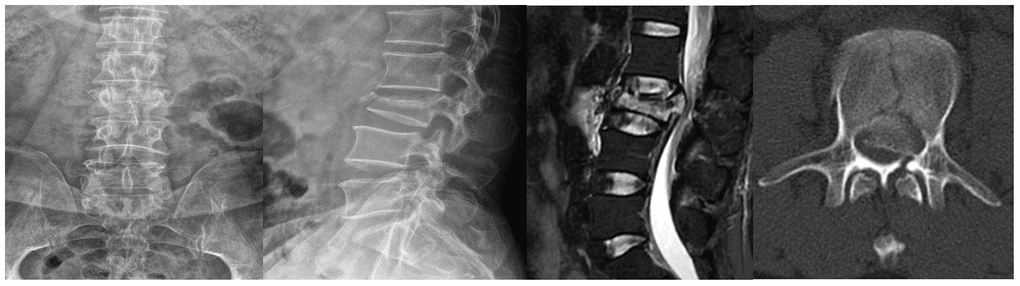

A 52-year-old male suffering with a L3 LBF presented with lower back pain and serious weakness in both lower limbs. The patient had history of shopping while wearing an ordinary mask. Physical examination indicated that his bilateral hallux dorsal extensor muscle strength level was 2, bilateral tibialis anterior muscle strength was level 2, bilateral quadriceps muscle strength was level 4, and bilateral iliopsoas muscle strength was level. X-ray, magnetic resonance imaging (MRI), and computed tomography (CT) examinations revealed an L3 LBF as well as severe spinal cord compression (Figure 1). The patient denied experiencing fever, cough, sputum production, dyspnea, nausea or vomiting. There was no significant lung abnormality on preoperative CT examination (Figure 2), and tests for viruses indicated the patient to be influenza a virus RNA (-), influenza b virus RNA (-), and respiratory syncytial virus RNA (-). Routine blood counts showed leucocytes 11.43 g/L, erythrocytes 4.87 g/L, hemoglobin 139 g/L, platelets 208 g/L, neutrophils 88.5%, lymphocytes 5.9%, monocytes 5.5%, eosinophils 0%, and basophils 0.1%.

Figure 1. Lumbar X-rays, MRI, and CT examinations of the patient.